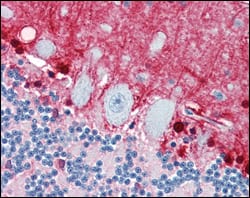

Product Image

| IHC | 1/200 - 1/1000 |